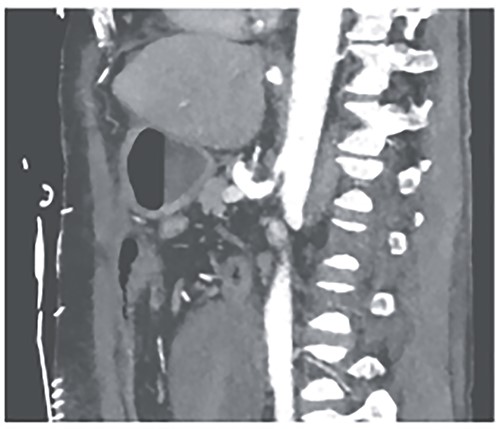

Postoperatively, the patient achieved hemodynamic stabilization in the intensive care unit. On the sixth postoperative day, there was a recurrence of circulatory collapse in addition to relevant bloody discharge through the drains. CT imaging once again revealed an active bleeding of the pancreaticoduodenal artery, which was successfully treated interventionally using coiling (Figs 2 and 3).

Postinterventional angiography, showing the aneurysm of the pancreaticoduodenal arcade, after interventional coiling.